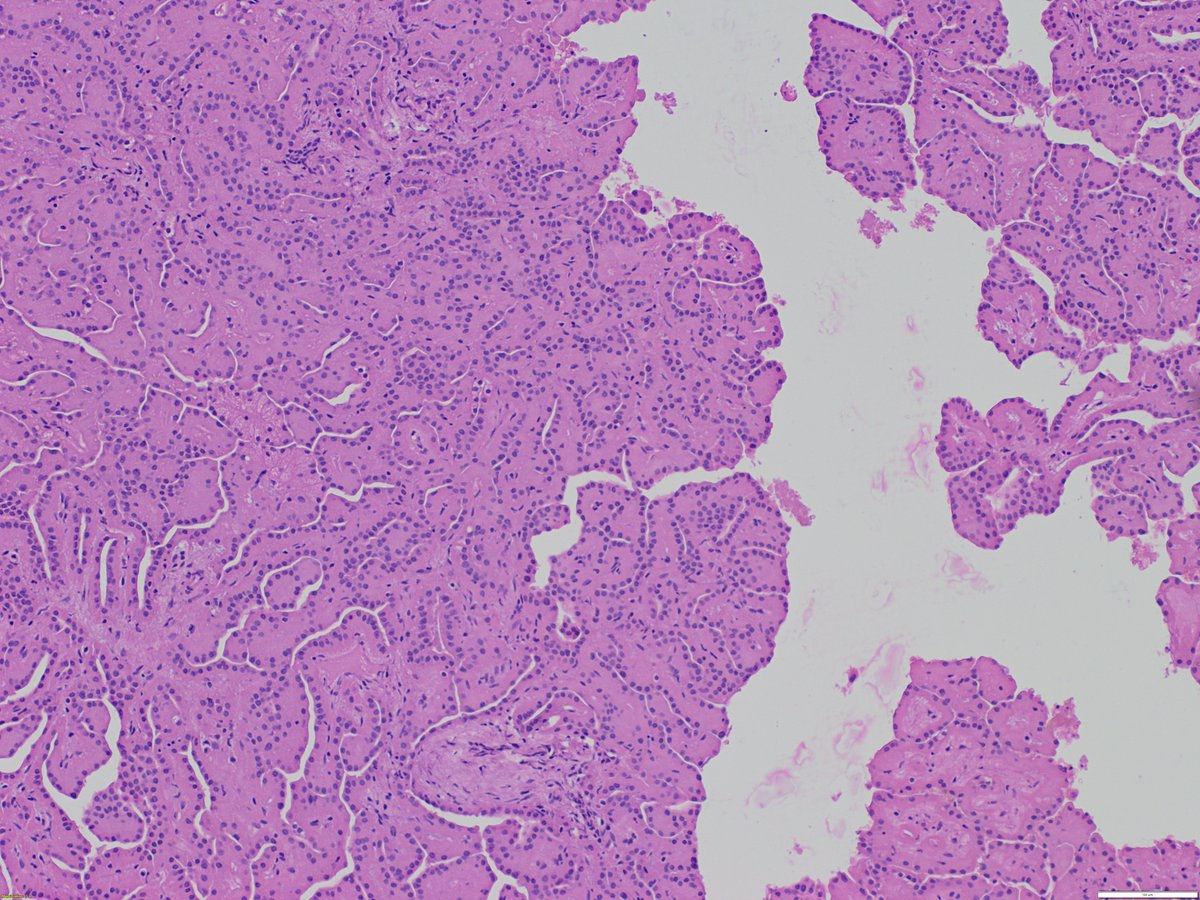

66/F incidental renal tumor.#renalpath @slusagar @rajalbshah @ashokparameswar @priyaraomd @atman_ci @TristanRutland7 More pics in the second tweet.

1

7